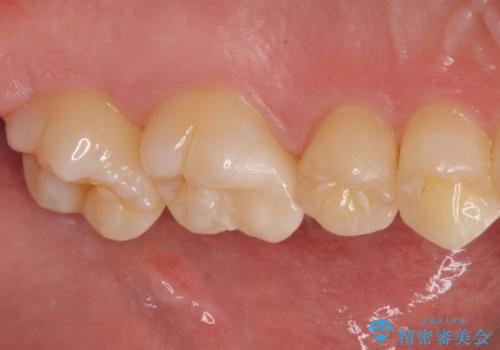

歯に穴が開いた セラミックインレー修復

- 当院でインビザラインによる矯正治療が終わった患者様です。

矯正治療終了時歯に穴が開いたとのことで、治療を希望されました。

拡大鏡視野化にて、虫歯を除去し、セラミックインレー(セラミックの詰め物)に適した形に整えました。

セラミックインレー装着時には、ラバーダム防湿にて装着をしています。